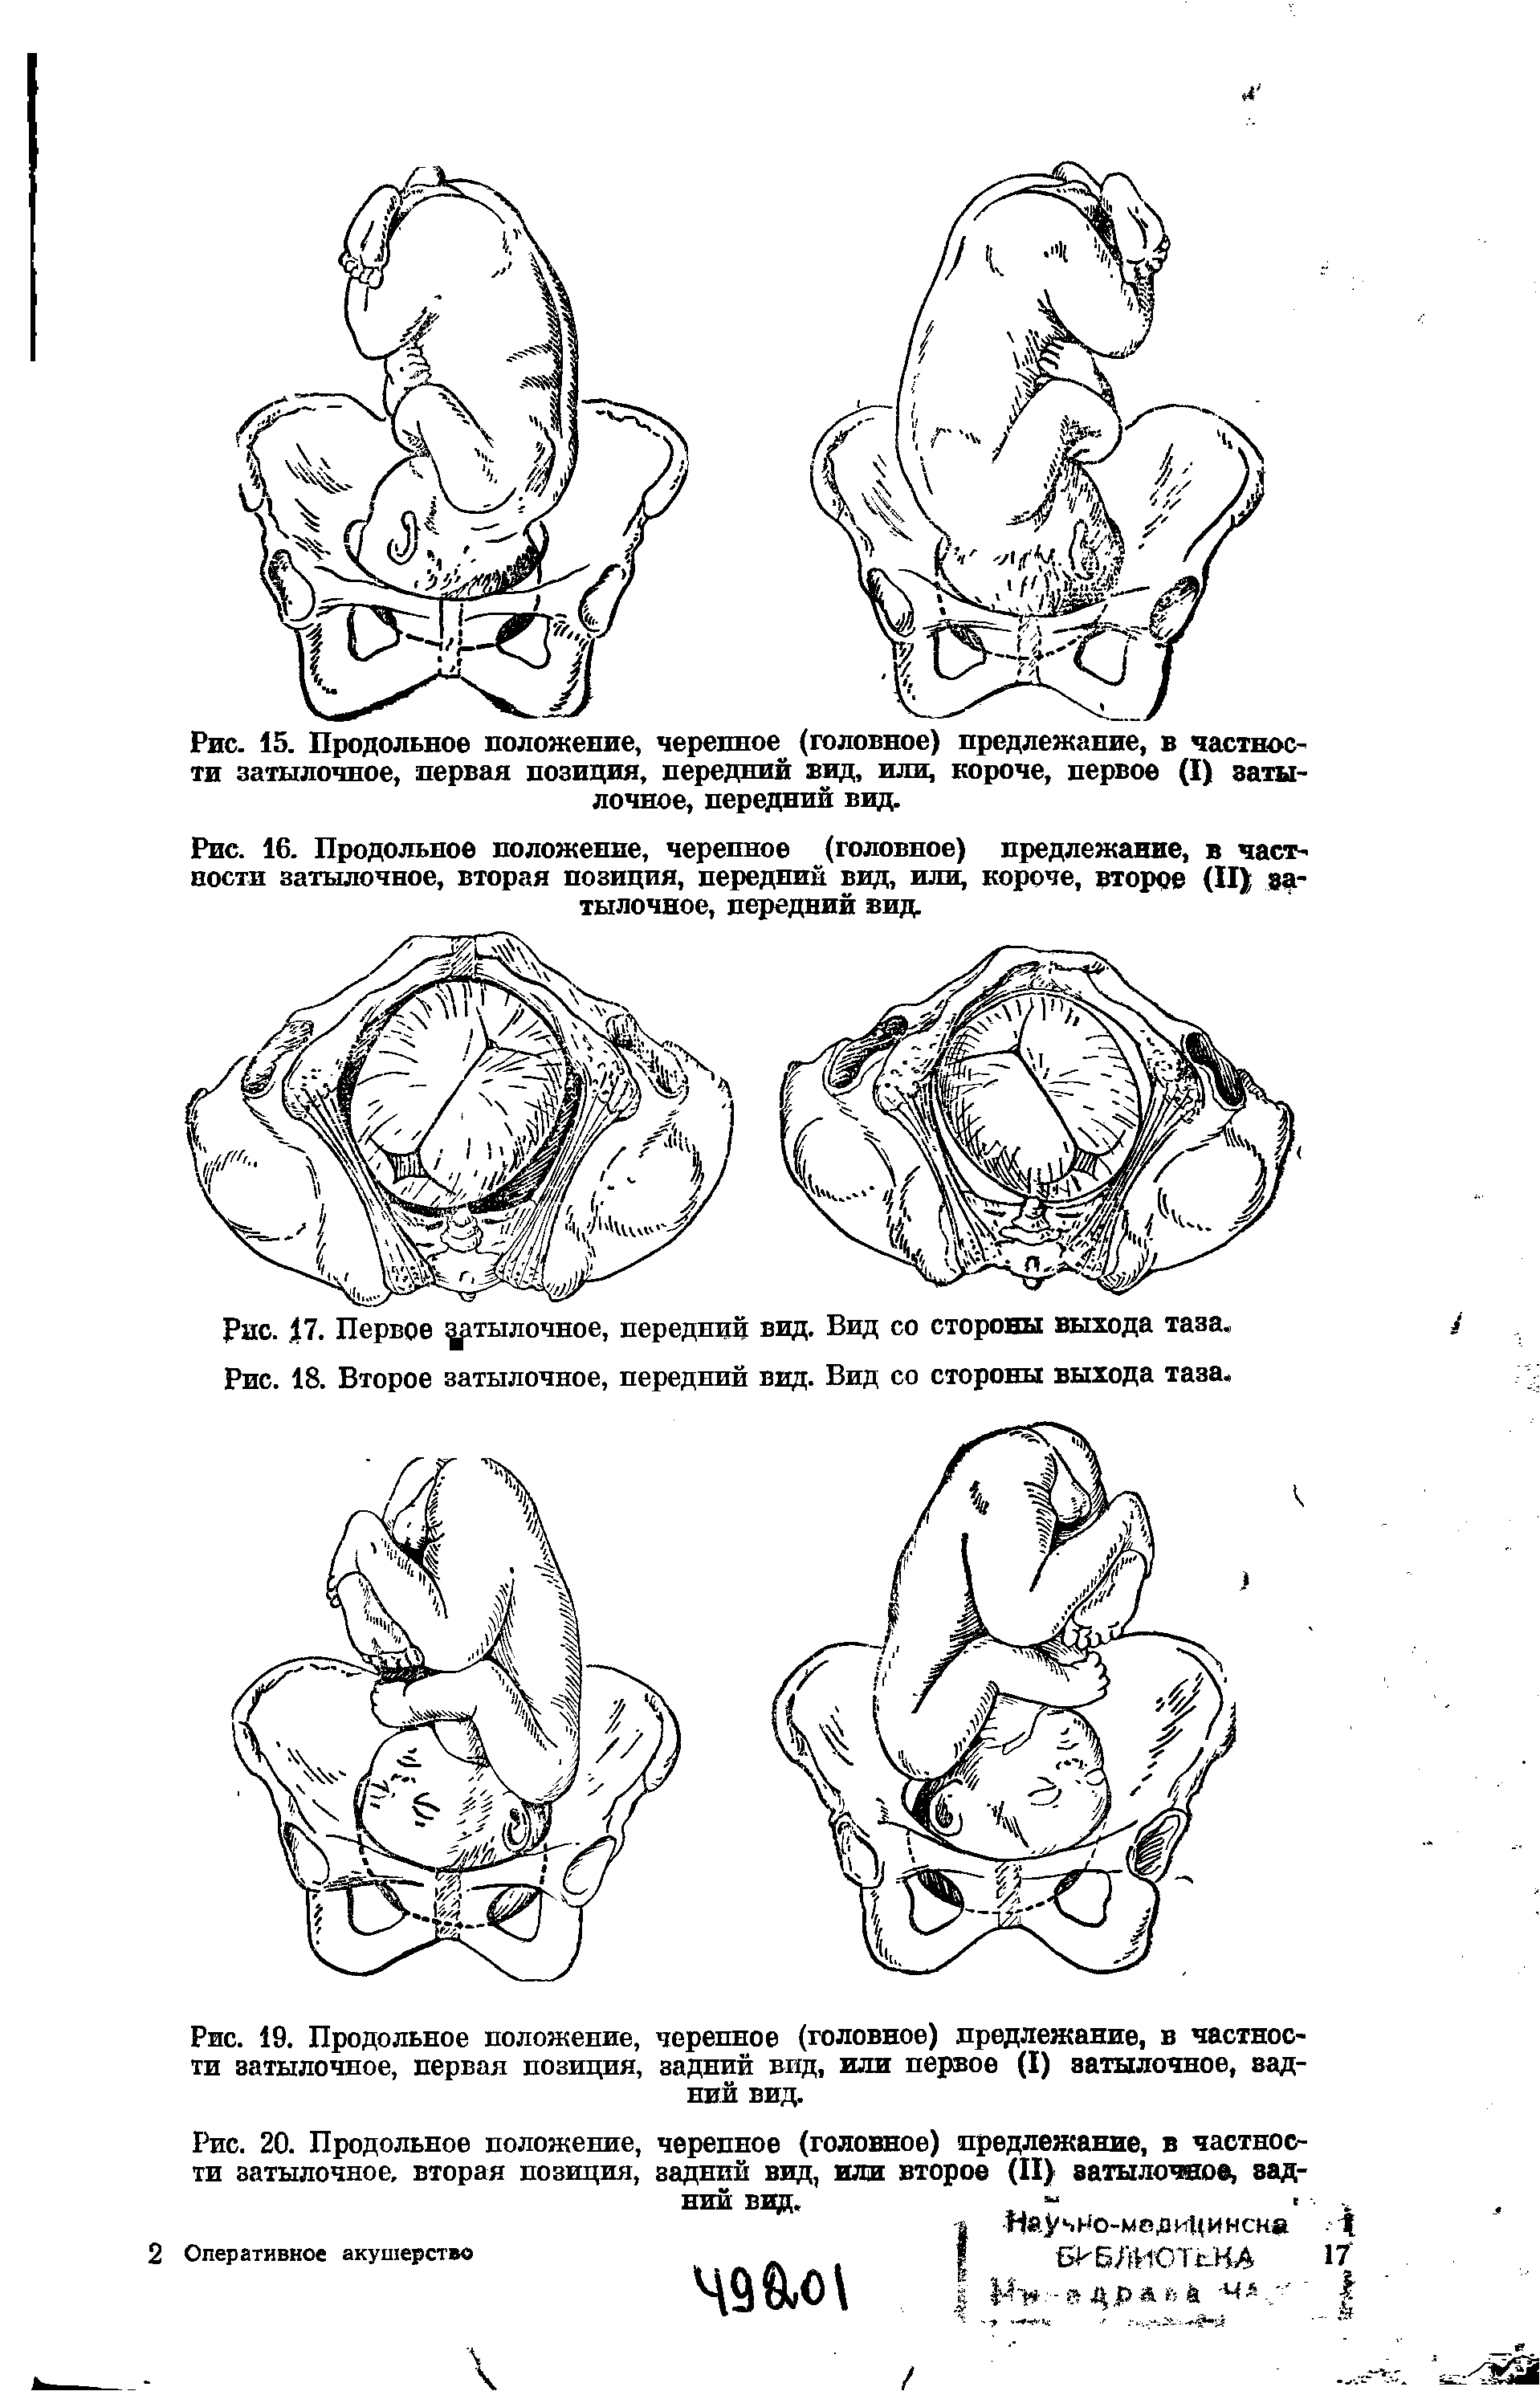

Во время беременности, положение плода имеет большое значение для мамы и малыша. Одним из типичных положений является продольное предлежание головное. В этом положении голова малыша находится внизу, а ножки - наверху. Это положение достаточно распространено и предпочтительно для естественных родов.

1 Позиция задний вид затылочного предлежания

1 Позиция передний вид затылочного предлежания

Задний вид затылочного предлежания биомеханизм родов

Фото положения плода во время беременности

Ниже приведены несколько фотографий, которые помогут вам визуализировать положение плода во время беременности.